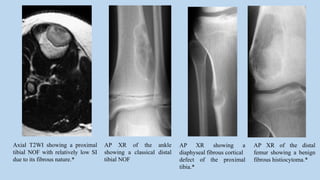

Axial T2WI showing a proximal

tibial NOF with relatively low SI

due to its fibrous nature.*

AP XR of the ankle

showing a classical distal

tibial NOF

AP XR showing a

diaphyseal fibrous cortical

defect of the proximal

tibia.*

AP XR of the distal

femur showing a benign

fibrous histiocytoma.*